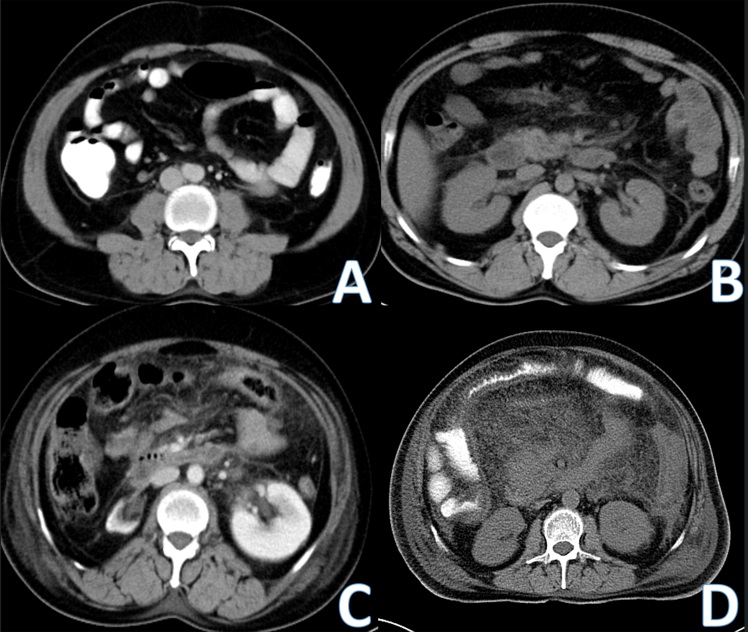

Figure: Figure 1. Representative contrast-enhanced CT images showing graded mesenteric inflammation in acute pancreatitis: (A) Type 0 – no visible changes in the mesentery; (B) Type 1 – focal changes involving the mesenteric root with vascular engorgement and fat stranding; (C) Type 2 – diffuse mesenteric fat stranding without mass effect; (D) Type 3 – diffuse mesenteric fat stranding with mass effect on adjacent structures.